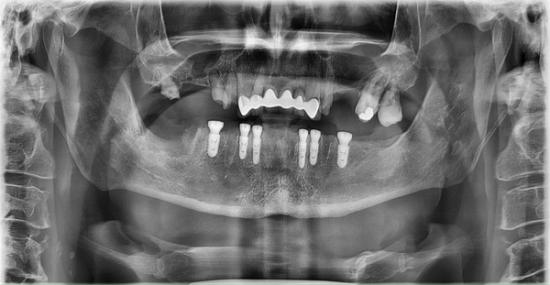

Before Photo